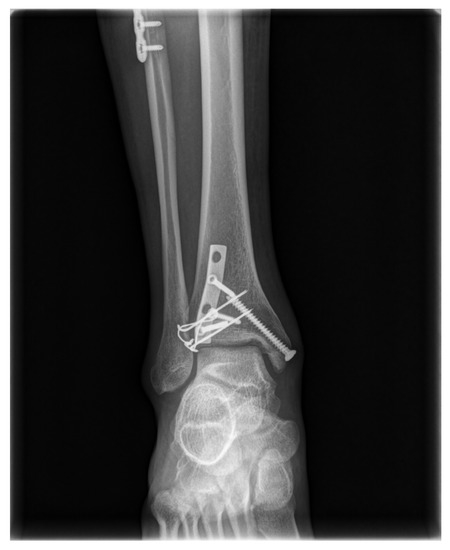

A Tension-Band Wiring Technique for Direct Fixation of a Chaput Tubercle Fracture: Technical Note

2. Surgical Technique